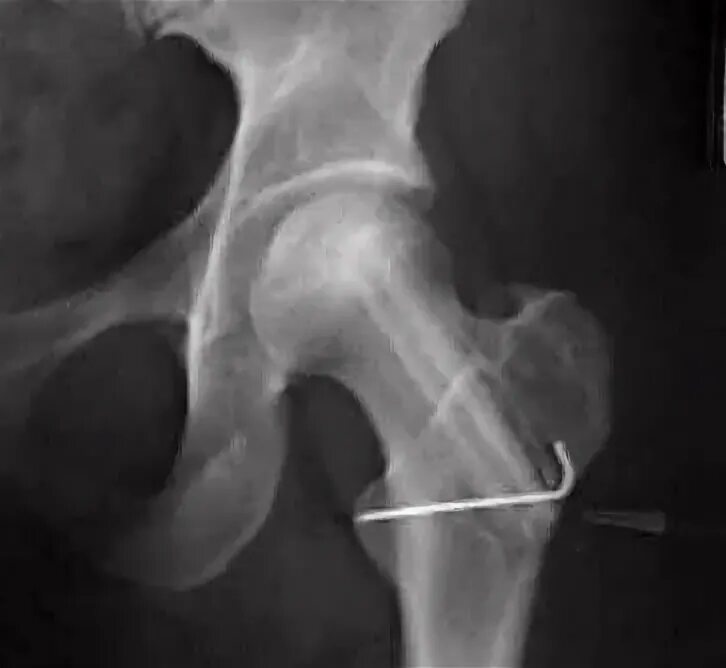

Некроз тазобедренного сустава лечение без операции